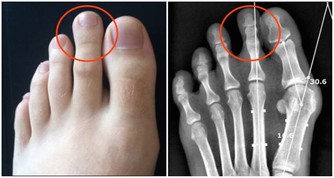

2.匙狀指

匙狀指也被稱為反甲,指甲變薄,中間像湯匙一樣凹陷,邊緣翹起。

除了外傷,常見於缺鐵性貧血、風濕熱或高原疾病。

匙狀指也可能是心臟疾病和甲狀腺機能減退的跡象。